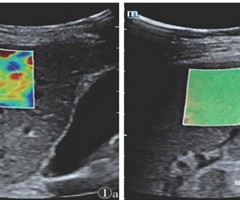

腮腺局灶性病变的多模态超声成像研究进展

[摘要]通过复习国内外多模态超声评估腮腺局灶性病变的最新相关文献,包括灰阶超声、CDFI、超声造影、弹性成像、影像组学、深度学习、预测模型等,总结腮腺局灶性病变的各种模态超声成像评估的优势和不足,以及病变的主要声像特征和相关参数,旨在提高该...